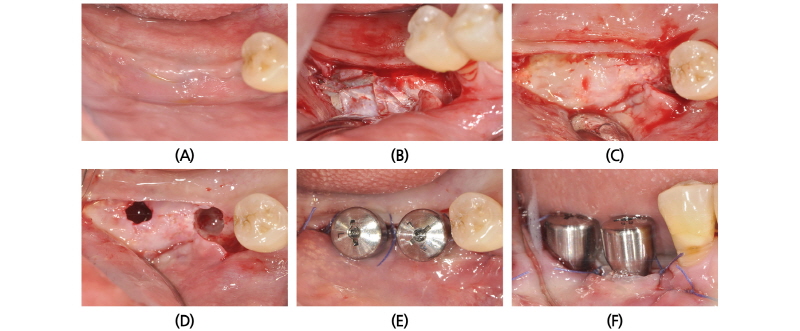

골유도 재생술을 시행한 후 5개월이 지난 후에 임플란트를 식립하도록 하였다. 우측 하악 구치부에 시행한 비흡수성 차폐막을 제거한 후(Fig. 9A~9C), 직경 5 mm 임플란트 2개를 각각 #46, #47 부위에 식립하였다(Fig. 9D~9F). 골질은 D1 정도였고 초기 고정도 잘 이루어졌다. 그 다음에는 우측 상악 구치부 수술을 진행하였다. Titanium mesh를 제거한 후(Fig. 10A~10D), #14, #15 부위에는 직경 4.5 mm 의 임플란트를 식립하였고, #16 부위에는 직경 5 mm 임플란트를 식립하였다(Fig. 10E, 10F). 골질은 D3 정도였으나 초기 고정을 얻는 데에는 큰 무리가 없었다.